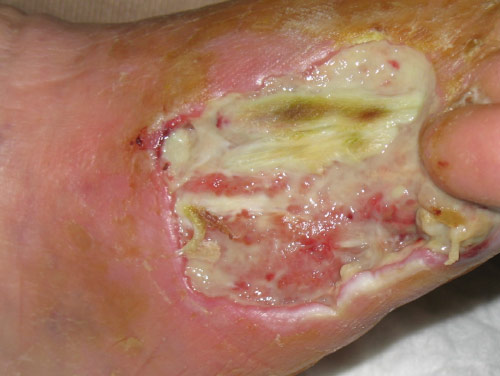

91 years old woman, still smoker, suffering from Büerger’s disease; due to ischemic gangrene of 4th and 5th toes of her right foot, she undergoes amputation. After about 3 weeks, surgical dehiscence is noted with a lot of necrotic tissue and exposure of the extensor tendon of the 3rd toe.

Post-amputation dehiscence with necrosis and tendon exposure.